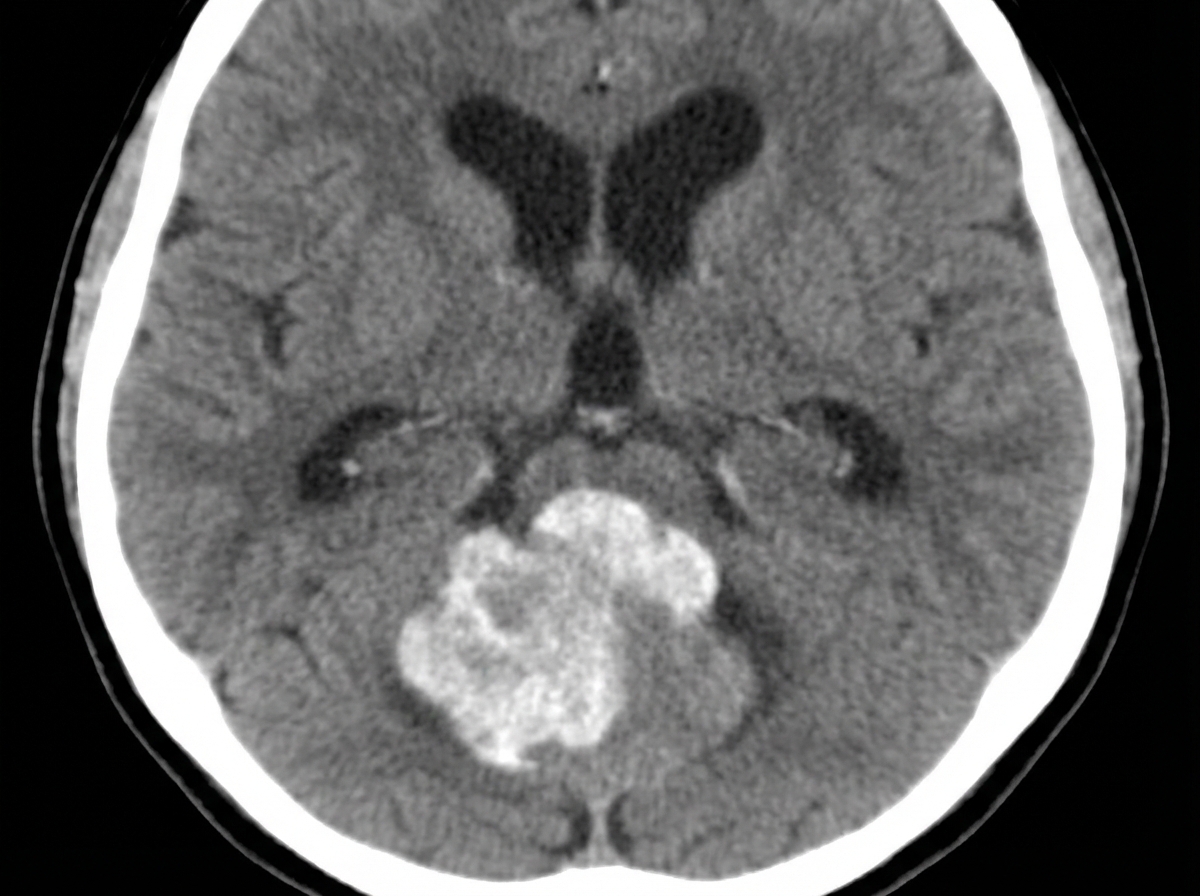

The given CT scan shows which brain lesion?

Explanation: ***Medulloblastoma*** - Appears as a **hyperdense, homogeneously enhancing mass** in the **cerebellar vermis** with compression of the **4th ventricle** and associated **obstructive hydrocephalus**. - Commonly presents as a **midline posterior fossa tumor** in children, often showing **calcifications** and **cystic components** on CT imaging. *Subdural hematoma (SDH)* - Appears as a **crescent-shaped collection** between the **dura and brain surface**, typically **hypodense** (chronic) or **hyperdense** (acute) on CT. - Located in the **supratentorial compartment** along the cerebral convexity, not in the **posterior fossa** or cerebellar region. *Brain abscess* - Characterized by a **ring-enhancing lesion** with a **hypodense necrotic center** and significant **perilesional edema** on contrast-enhanced CT. - Typically shows a **thin, smooth wall** with enhancement and may have **gas bubbles** within the lesion, unlike the solid appearance of medulloblastoma. *Oligodendroglioma* - Appears as a **well-demarcated, heterogeneous mass** with characteristic **"eggshell" calcifications** in the **cerebral hemispheres**, particularly **frontal and parietal lobes**. - Typically located in the **supratentorial compartment** rather than the **posterior fossa**, and shows less enhancement compared to medulloblastoma.